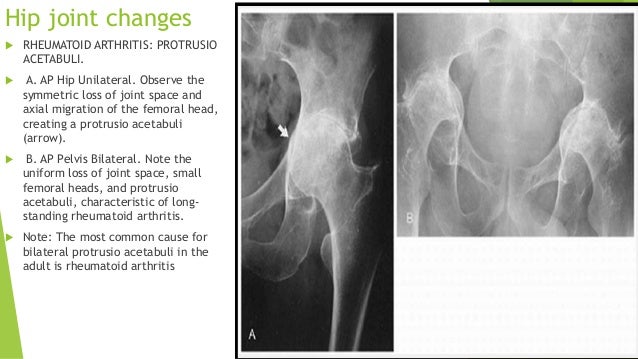

Each person with ra is affected differently.

Rheumatoid arthritis bilateral or unilateral. Herein we report a case of rheumatoid arthritis with unilateral knee synovial hypertrophy in hemiplegia. Read more about common ra symptoms from webmd including pain stiffness fatigue weakness and more. Arthritis is an umbrella term used to describe inflammation of the joints. To the best of our knowledge this is the first case of unilateral rs3pe in a patient of rheumatoid arthritis while on drugs.

Although the disorder is usu ally idiopathic it can also be associated with ra and other systemic diseases. An autoimmune disorder rheumatoid arthritis occurs when your immune system mistakenly attacks your own body s tissues. If a right hemiplegic patient has recurrent pain on the left knee and synovial hypertrophy and fails to respond to treatment for osteoarthritis early detection by evaluation for rheumatic disease is crucial to prevent severe sequelae influencing rehabilitation of hemiplegia. Episcleritis is inflammation of the epis clera which lies just beneath tenon s capsule.

This case also adds to clinical aspect according to which rs3pe is considered as a distinct clinical entity than rheumatoid arthritis as rs3pe occurred in a patient regularly taking dmard. Often the patient first notices stiffness in one or more joints usually accompanied by pain on movement and by tenderness in the joint. The symptoms of rheumatoid arthritis can come and go. It is bilateral 40 of the time and man ifests with salmon pink eyes and mild pain.